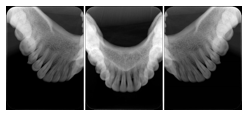

2 Occlusal Vertical Maxilla A Dental Image Layout

DL-C001A

Reference: DL-C001-U1L0

Reference: DL-C001-U2L0

00

Occlusal

18, 17, 16, 15, 14, 13, 12, 11, 13, 12, 11

01

21, 22, 23, 24, 25, 26,27, 28

2 Occlusal Vertical Mandible A Dental Image Layout

DL-C002A

Reference: DL-C002-U0L1

Reference: DL-C002A-U0L2

10

48, 48, 47, 46, 45, 44, 43, 42, 41

11

31, 32, 33, 34, 35, 36, 37, 38

2 Occlusal Horizontal Maxilla A Dental Image Layout

DL-C003A

Reference: DL-C003-U1L0

Reference: DL-C003-U2L0

18, 17, 16, 15, 14, 13, 12, 11, 13, 12, 11, 21, 22, 23, 24, 25, 26,27, 28

2 Occlusal Horizontal Mandible A Dental Image Layout

DL-C004A

Reference: DL-C004-U0L1

Reference: DL-C004-U0L2

48, 48, 47, 46, 45, 44, 43, 42, 41, 31, 32, 33, 34, 35, 36, 37, 38